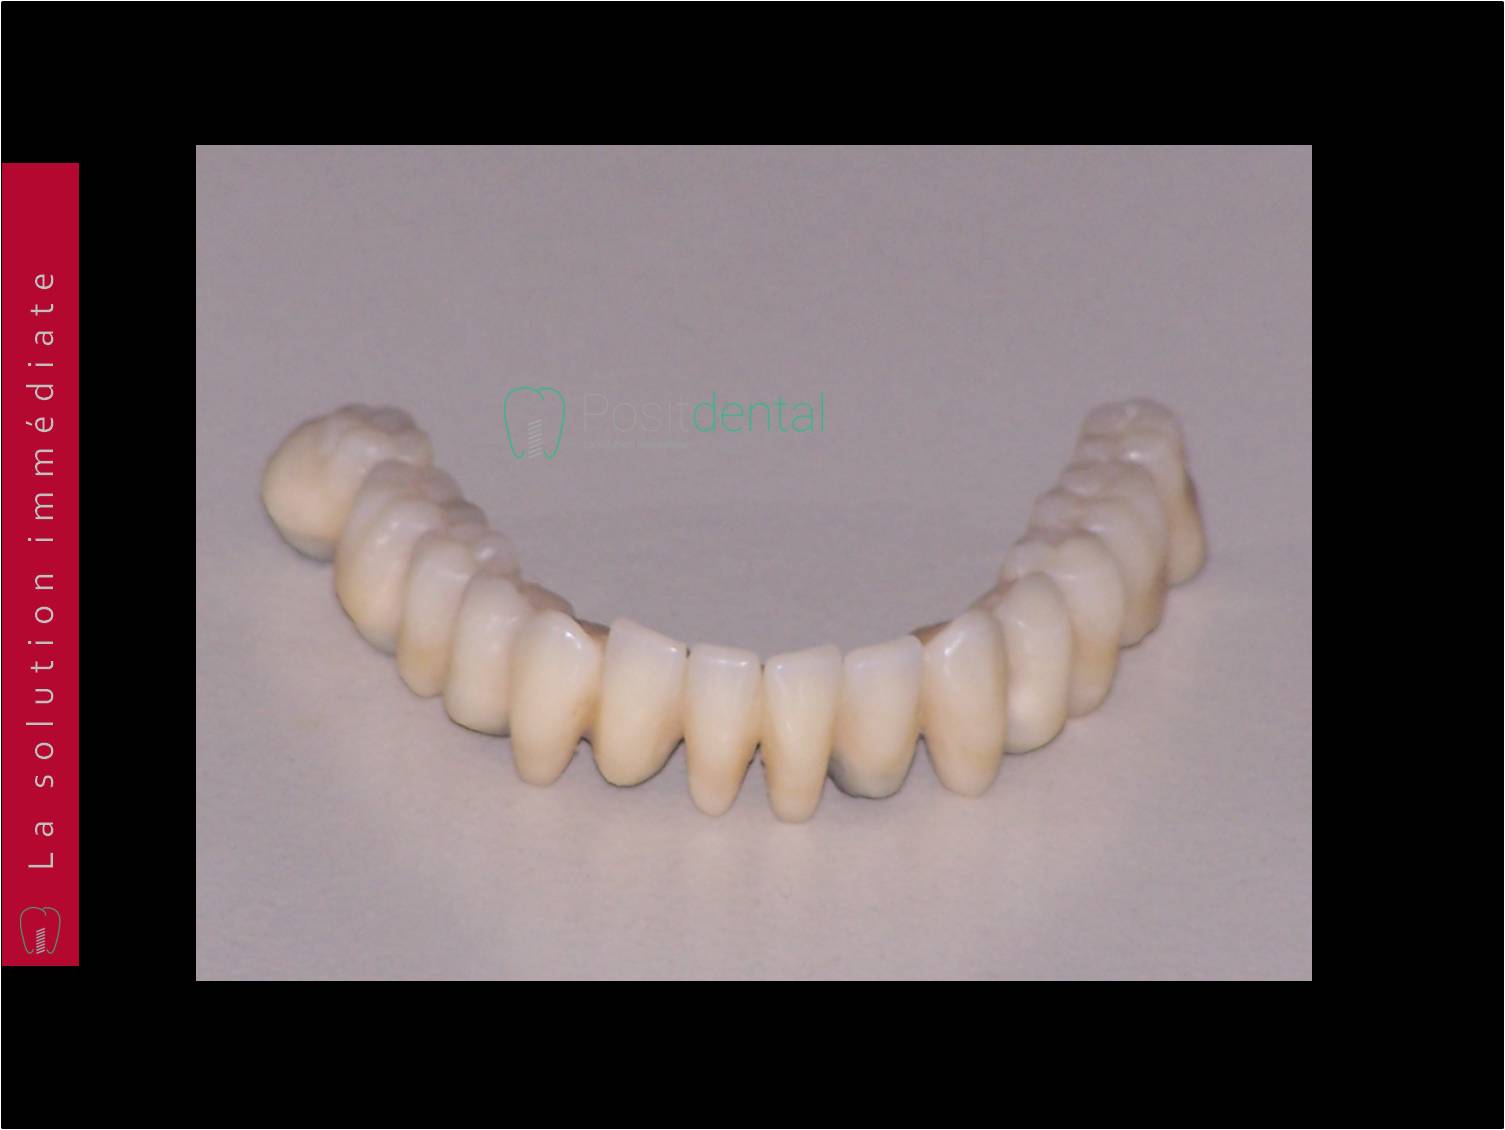

Bridge immédiat posé dans la continuité de la pose des implants

Uya2oirluigh1vu3fex4y70uezce - Eugenol

Tu me demande les photos du cas et ton seul commentaire est de poster une photo de ton provisoire :)

Pour montrer qu'il est plus joli que le mien ? Et bien c'est vrai, je le trouve pas mal.

Cas bi-max réalisé selon le protocole de Dimitri, entierement délégué, pour une fois, a vivien, laboratoire LIO. Planif et guide réalisé avec Co-diagnostic, bridge prov PMMA rosenscrew réalisé en amont de la chirugie.